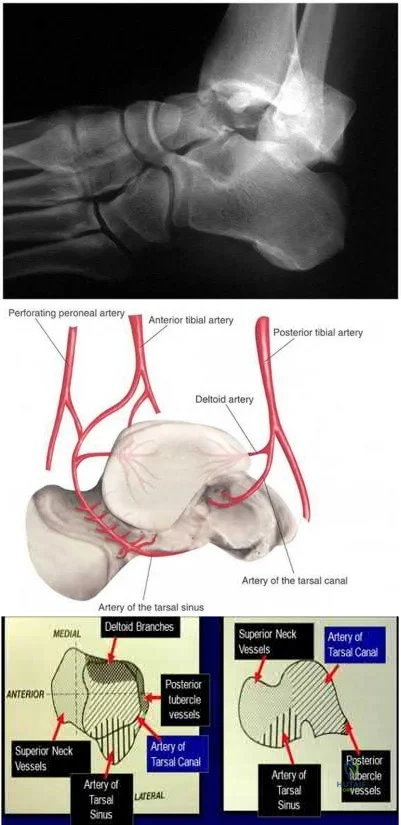

A 29-year-old male sustains the isolated lower extremity injury shown in Figure A. During open reduction, what structure must be kept intact in order to protect the remaining blood supply to the talar body?

The review article by Fortin et al discusses talar blood supply, injury mechanisms and classifications, and treatment options. They state that the main artery to the body of the talus is the artery of the tarsal canal, which is a branch of the posterior tibial artery. The peroneal and anterior tibial artery also contribute branches to the talus.

Illustration A and B show the arterial network of the talus.